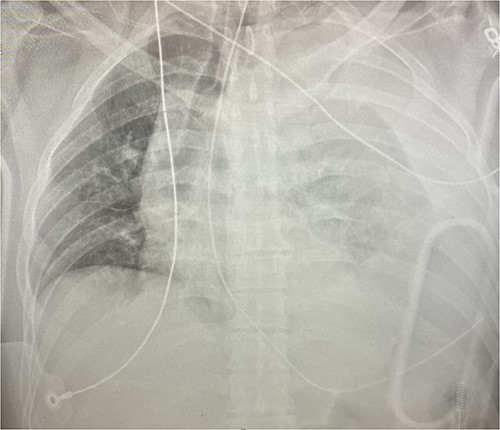

Given his hemodynamic normalization without ongoing transfusion requirements, he was taken to the computed tomography (CT) scanner for axial imaging of the head, chest, abdomen and pelvis. A CT angiogram of the chest revealed trace pneumopericardium and pneumomediastinum with trace hemopericardium. A 1.7 × 0.7 cm out-pouching at the anterior aspect of the right ventricular apex concerning for a traumatic pseudoaneurysm was also detected (see Figs 2 and 3). His other injuries were notable for subarachnoid and subdural hemorrhages, left temporal bone fracture, open mandibular fracture, left 3–6th, 10th and 11th rib fractures, a 4th lumbar vertebrae burst fracture with 1st and 3rd lumbar vertebrae compression fractures, 8–11th thoracic vertebrae compression fractures, and a left femoral neck fracture. He was subsequently transferred back to the trauma bay where a formal trans-thoracic echocardiogram was immediately performed, which demonstrated a dyskinetic area of the right ventricular apex with paradoxical out-pouching during systole—suggestive of pseudoaneurysm and confirming the diagnosis on axial imaging.

Sagittal CT imaging demonstrating pseudoaneurysm of right ventricular free wall rupture.